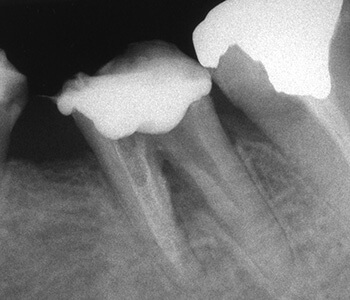

根の側壁に穴が開いて感染していることにより、前後の根の間の骨が吸収してなくなっています。

根の先端部分が著しく破壊しており、その周囲の骨もかなり吸収しています。